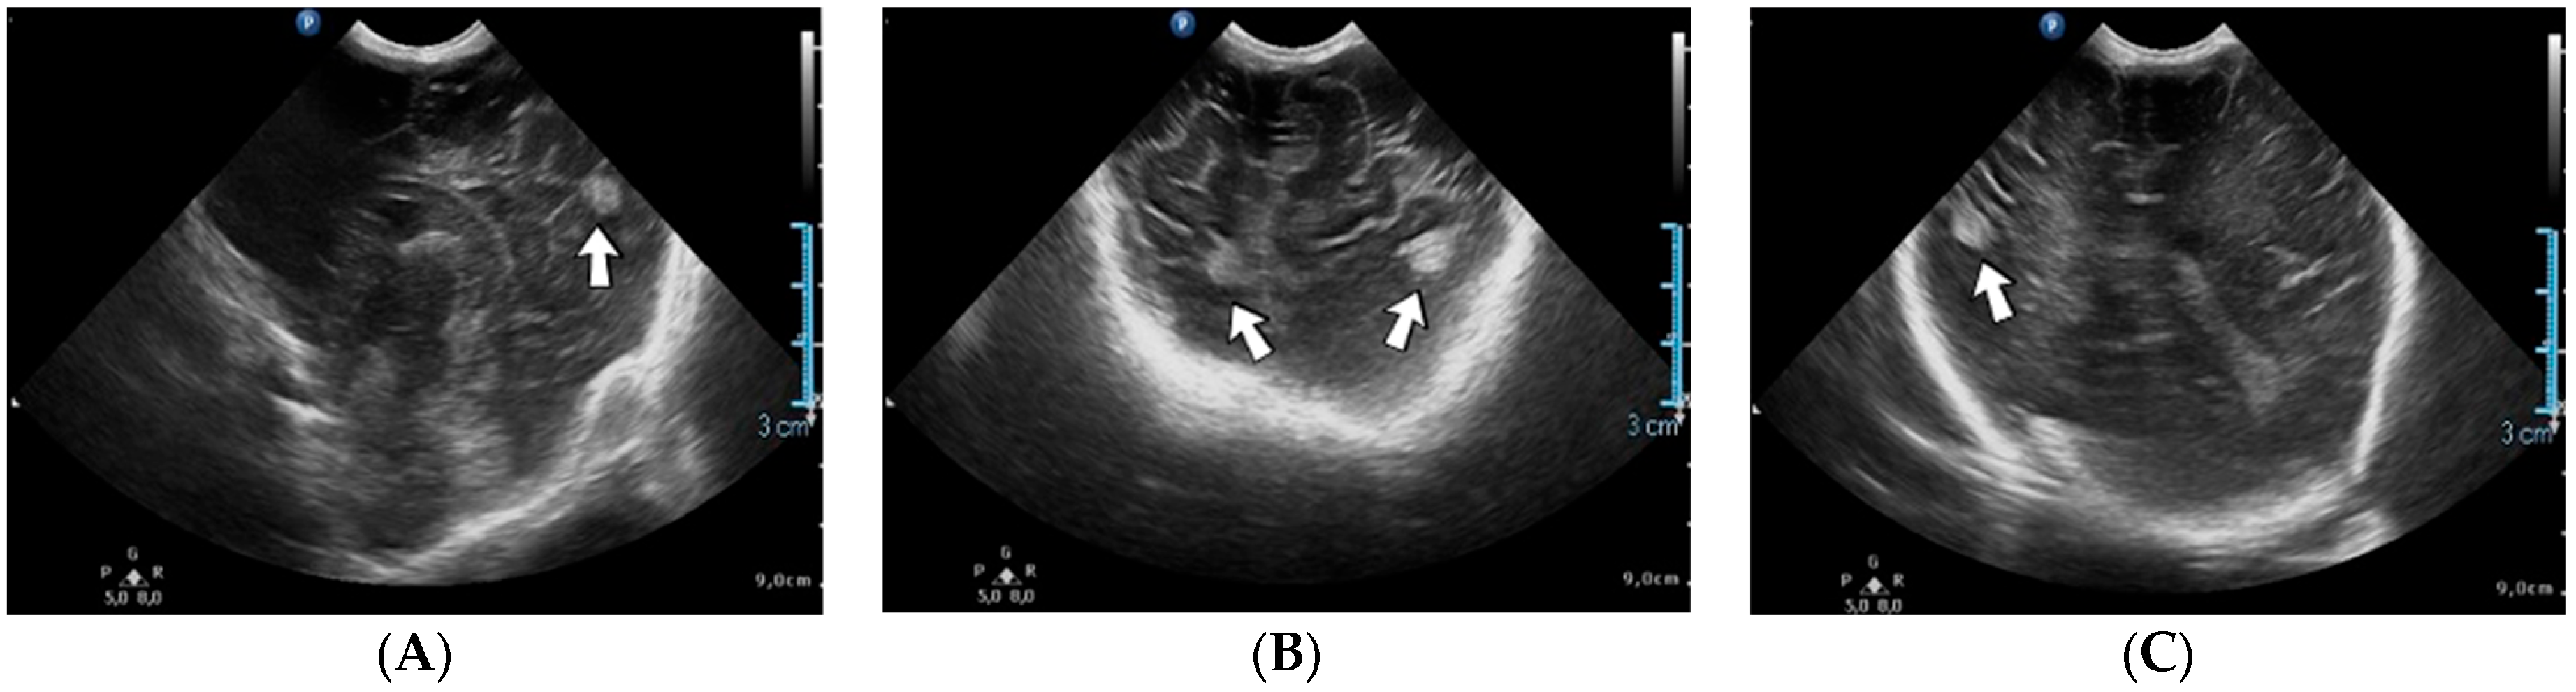

A 13-day-old female neonate (33 weeks, 1.50 kg) presented with a suspicion of a left pulmonary sequestration, confirmed on an admission CT scan, and severe pulmonary hypertension. Two weeks after admission, the patient developed severe bradycardia. A head ultrasound after the event indicated various hyperechoic lesions in the left temporal and parietal lobes and right insular and parietal lobes (Figure 7). The laboratory findings from that time showed anemia and elevated, but decreasing c-reactive protein. A lumbar puncture was performed, with a normal result.

Figure 7.

Cerebral thromboembolism on brain ultrasound: parietal lobes (A–C).

Genetic testing confirmed inherited thrombophilia, with a positive MTHFR A1298C heterozygous gene mutation and Antithrombin deficiency. There was a positive maternal history of miscarriage before this pregnancy.